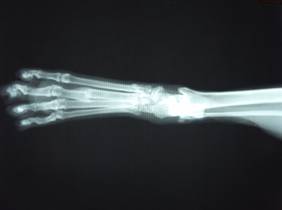

約2カ月後の様子。

足の痛みは全くなく自由に歩き回っている。

レントゲン検査でも、充分な仮骨が形成されている。

(仮骨=骨折が治っていく段階でできてくる新しい骨の組織)

43-04